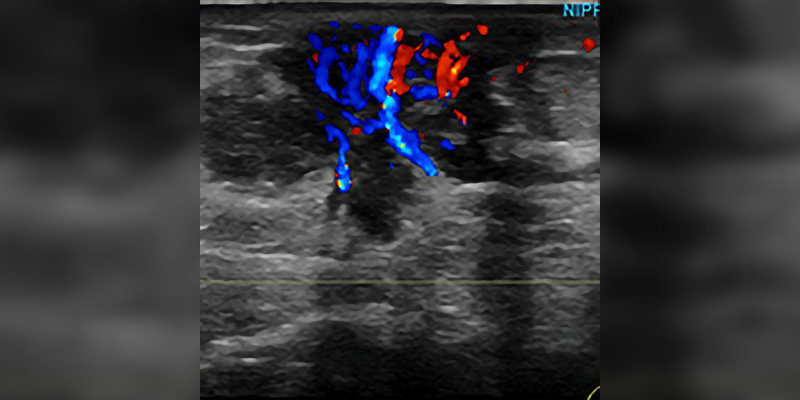

The following study materials and resources are suggested by experienced R.T.s to help you prepare for the breast ultrasound certification exams offered by the American Registry of Radiologic Technologists and the American Registry for Diagnostic Medical Sonography.